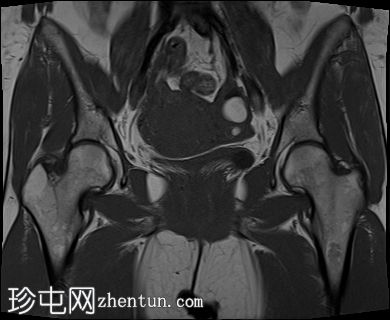

冠状位

T2加权像

子宫前壁交界区局灶性增厚,边界不清。形成直径约3厘米的局灶性肿块样病变,轻度压迫膀胱。肿块边界模糊不清,可见多个细小出血灶,在T1加权像和T2加权像上均呈高信号,提示局灶性子宫腺肌症。

子宫体前壁可见另一处病灶,位于上述病灶尾侧,边界清晰(有包膜)。该病灶在T1和T2加权像上均呈低信号,内部未见异常信号灶,周围可见少量明显血管通道,提示为小型子宫肌瘤。

左侧卵巢可见数个小囊肿,在T1加权像上呈高信号,在T2加权像上呈低信号(T2阴影),T1脂肪抑制序列未见信号下降,提示其为血液降解产物。最大的囊肿轴位大小约为3.1×1.7 cm,轻度压迫卵巢实质。

右侧卵巢可见黄体囊肿。未见实性肿块。

边界模糊不清是局灶性子宫腺肌症(无包膜)的特征。此外,病灶内存在多个微小的内部出血灶(异位腺体),且邻近增厚模糊的交界区,这些都是局灶性子宫腺肌症的诊断标准。

在上述病灶尾侧可见另一处具有不同影像学特征的病灶,该病灶边界清晰(有包膜),且信号均匀(无微小的内部出血灶),提示可能合并子宫肌瘤。

少数左侧卵巢囊肿伴有上述出血信号,可能代表子宫内膜异位囊肿,因为多发性和双侧性更倾向于子宫内膜异位囊肿而非出血性囊肿。